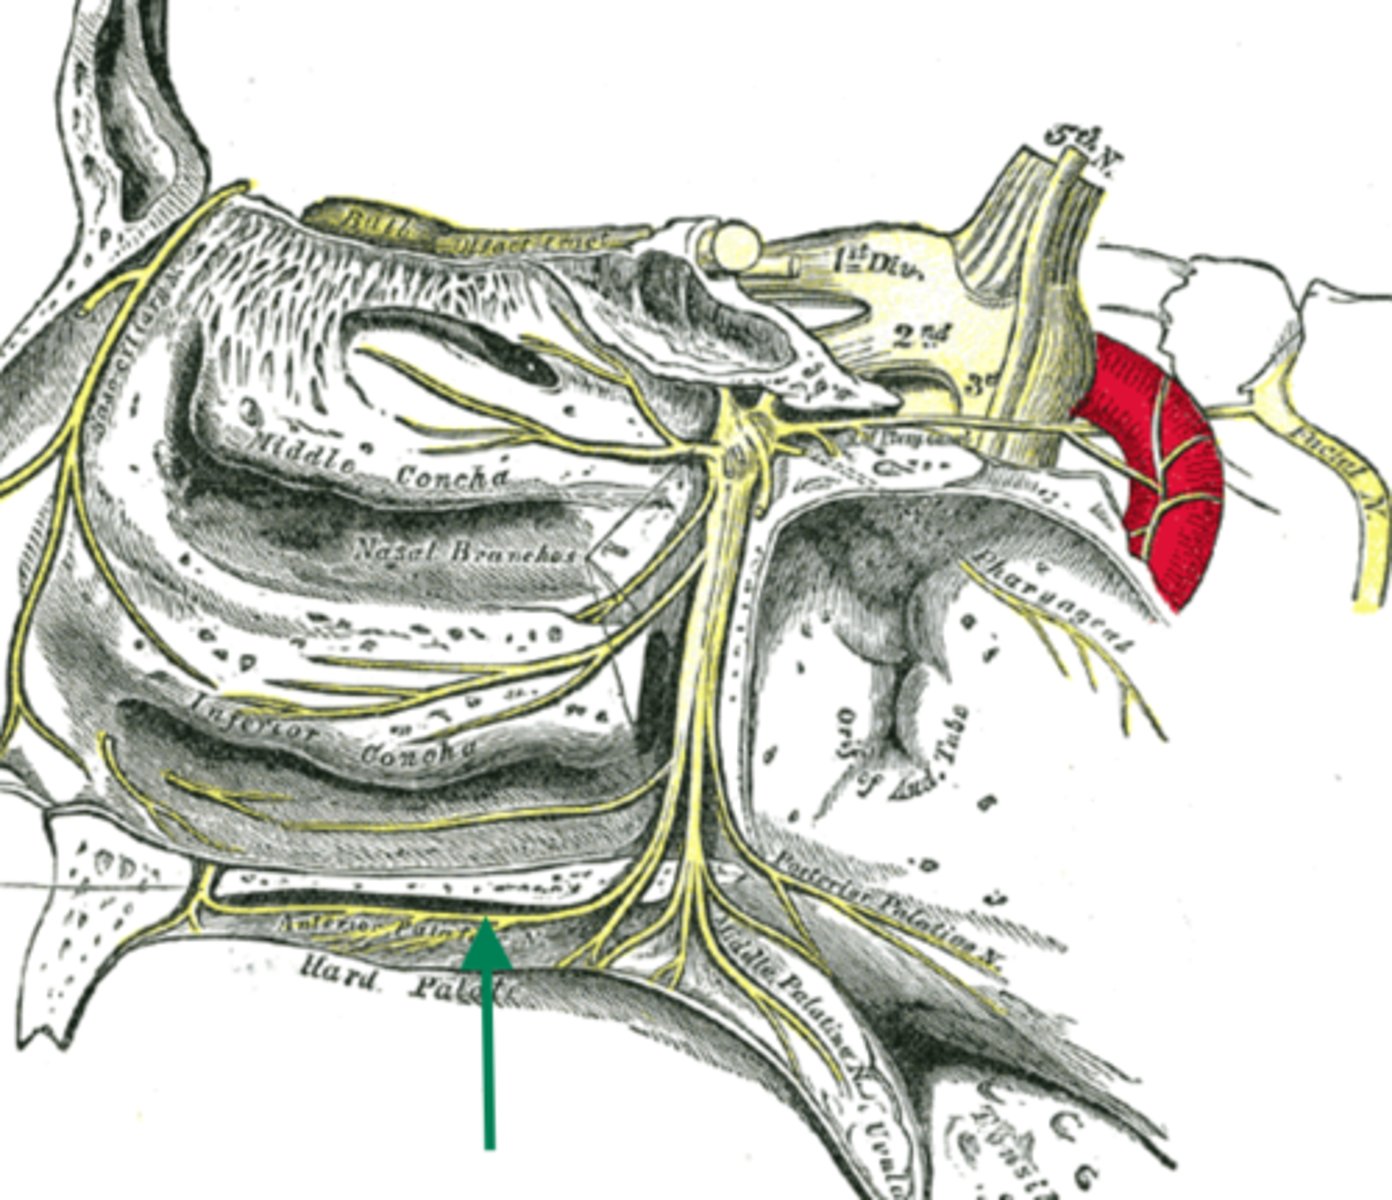

hard palate

anterior cranial fossa

palatine bone (horizontal plate)

maxilla (palatine process)

greater palatine nerve

greater palatine artery

greater palatine foramen

lesser palatine nerve

lesser palatine artery

greater and lesser palatine nerve

greater palatine nerve